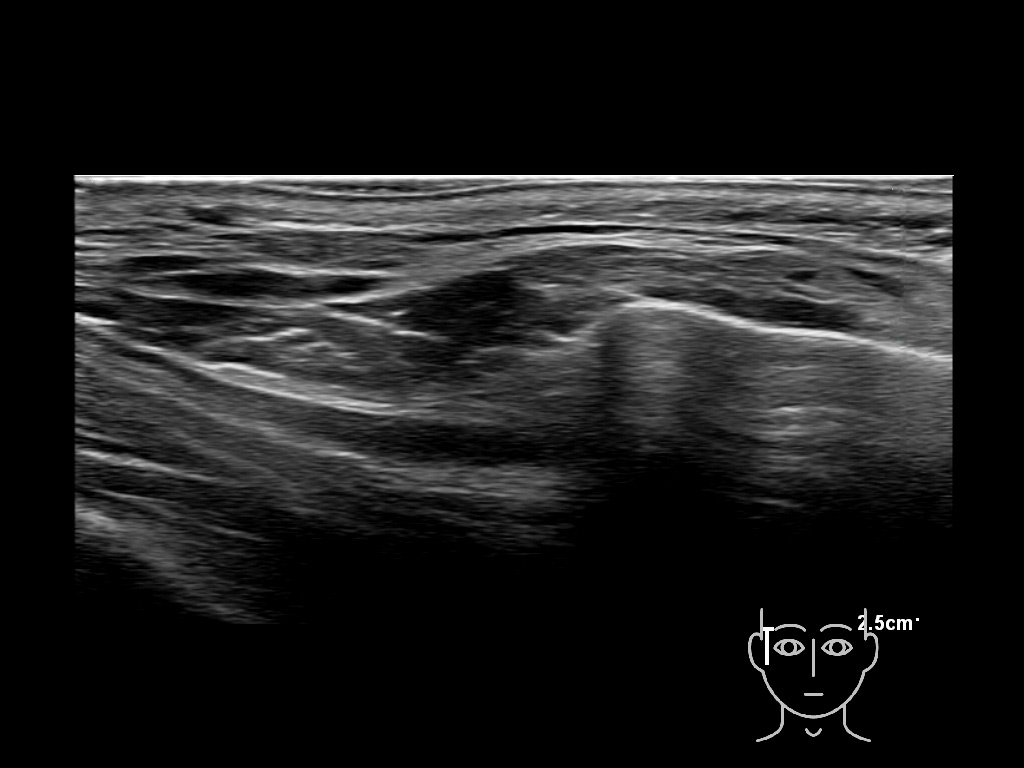

Filler behavior - Temple zygoma US

Study the first image to recognize the different layers. If you are sure about the layers, swipe to the second image to view the answer (if applicable).